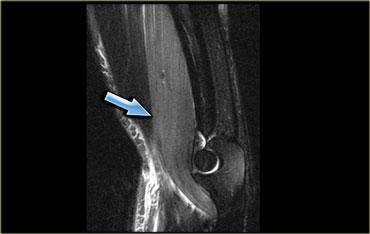

Bên trái là một bệnh nhân khác cũng bị đứt hoàn toàn gân cơ hamstring.

Có hình thái phù nề ngoại mạc cơ và kích thích thần kinh tọa.

Có thể xảy ra hội chứng hamstring.

Đây là tình trạng đau do sự hình thành sẹo sau chấn thương xung quanh thần kinh tọa (mũi tên).